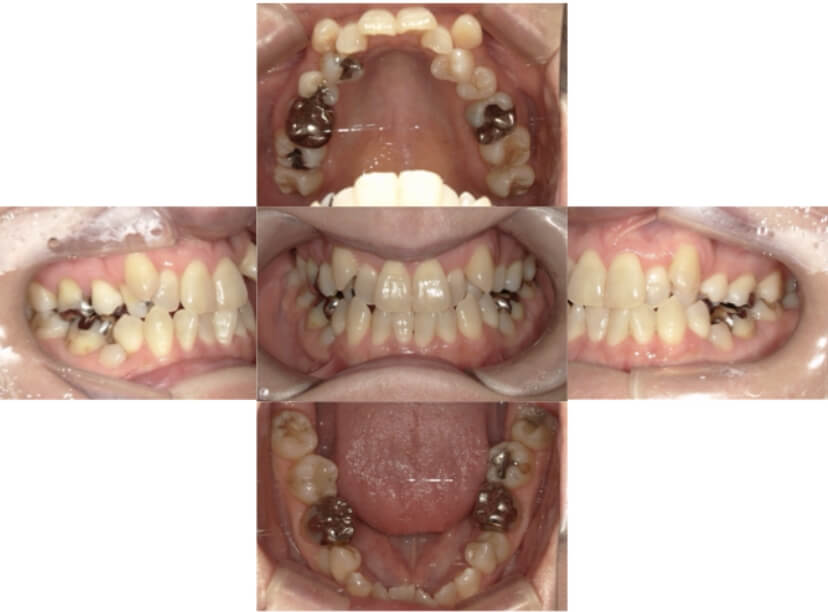

BEFORE

AFTER

上下顎叢生(上下の前歯のガタガタ)のケースです。

装置はラビアル(上下表側)で、上下顎の小臼歯を4本抜歯を行っています。抜歯したスペースを使って、上下の前歯の後方移動と叢生(ガタガタ)の改善を行っています。

主訴 八重歯を治したい。

年齢・性別 25歳 女性

お住まいの地域 神奈川県川崎市

治療方針 抜歯スペースを利用して上前歯の叢生(ガタガタ)の改善

抜歯部位 上下顎左右第一小臼歯

使用装置 ラビアル(上下表側)、顎間ゴム

治療期間 1年11か月

治療回数 16回

リテーナー クリアリテーナー